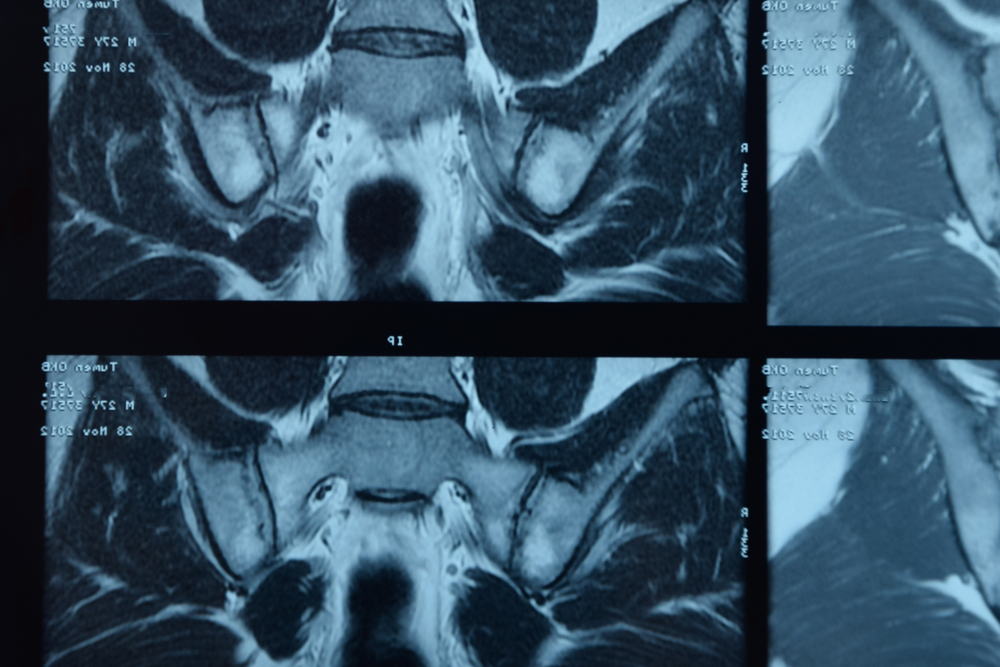

Rezonans magnetyczny miednicy jest jednym z najdokładniejszych badań obrazowych stosowanych w diagnostyce schorzeń narządów położonych w obrębie miednicy mniejszej. Dzięki wysokiej rozdzielczości i możliwości oceny tkanek miękkich bez użycia promieniowania jonizującego, rezonans odgrywa kluczową rolę w rozpoznawaniu chorób nowotworowych, stanów zapalnych oraz zmian anatomicznych. Rezonans miednicy znajduje zastosowanie zarówno u kobiet, jak i u mężczyzn, często stanowiąc uzupełnienie lub kolejny etap diagnostyki po badaniu USG lub tomografii komputerowej.

Rezonans magnetyczny (MRI) miednicy to nieinwazyjne, bezpieczne badanie obrazowe, które pozwala na bardzo dokładną ocenę struktur anatomicznych znajdujących się w obrębie miednicy mniejszej. W przeciwieństwie do badań wykorzystujących promieniowanie rentgenowskie, rezonans magnetyczny opiera się na działaniu silnego pola magnetycznego oraz fal radiowych, dzięki czemu nie obciąża organizmu promieniowaniem jonizującym.

MRI umożliwia ocenę tkanek miękkich z dużą precyzją, co ma szczególne znaczenie w diagnostyce chorób narządów rozrodczych, układu moczowego, jelit oraz struktur naczyniowych i mięśniowych miednicy. Rezonans magnetyczny miednicy może być wykonywany zarówno bez użycia środka kontrastowego, jak i z jego podaniem dożylnym. Kontrast poprawia widoczność zmian patologicznych, takich jak guzy, stany zapalne czy nieprawidłowości naczyniowe, i jest stosowany wtedy, gdy lekarz potrzebuje dokładniejszej oceny charakteru wykrytych zmian.